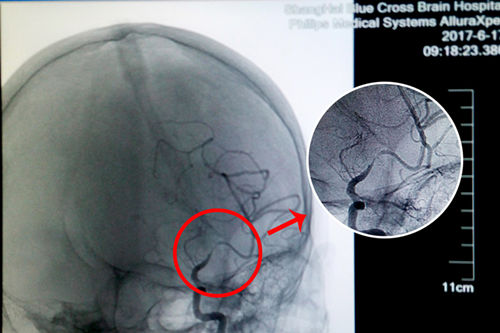

术前DSA影像显示,患者大脑中动脉血管70%以上狭窄

更为严重的是,入院后在DSA检查中还发现患者左侧大脑中动脉已经出现70%以上的狭窄,非常危险。李振并主任解释,脑血管狭窄是造成缺血性脑血管病的一个重要病因和危险因素,脑血管狭窄使得经过脑血管的血液减少,脑细胞就会缺血死亡。在临床上,脑血管狭窄程度在50%以下通过药物治疗,在50%-70%之间就要进行通过血管介入进行腔内血管成形术(球囊扩张支架置入术),而70%以上必须马上通过血管介入进行腔内血管成形术(球囊扩张支架置入术),否则一旦脑细胞因缺血大量死亡,患者会有性命之忧。